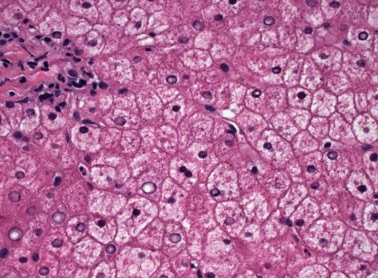

| Figure 2. Swollen and rarified hepatocytes with compressed sinusoids. |